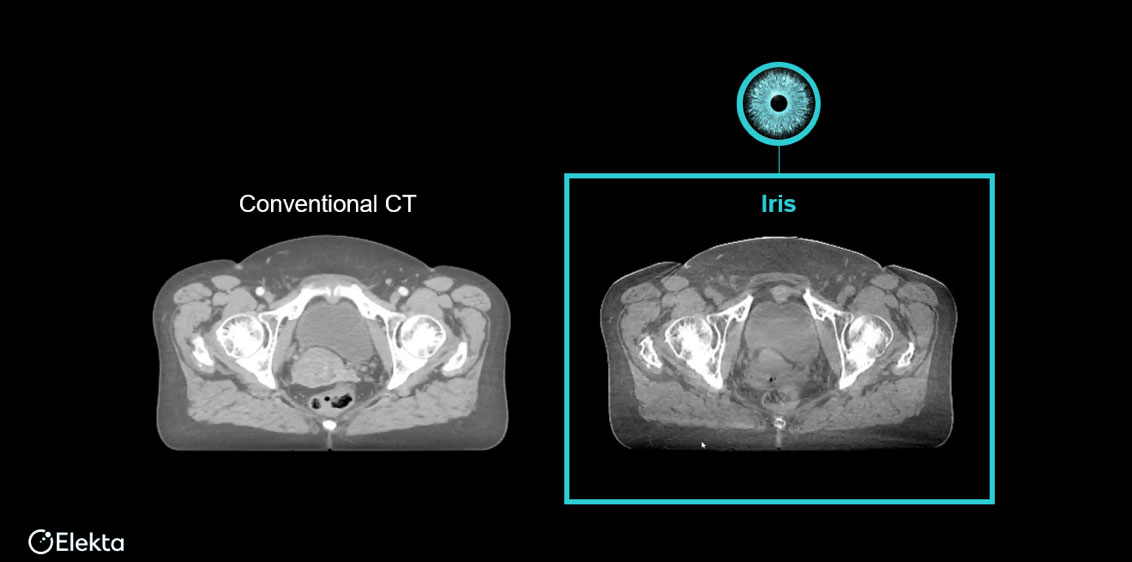

Iris® 高清AI增强影像通过全新解剖特异性AI散射校正与PolyQuant CT重建算法,从根源攻克传统CBCT散射干扰、软组织对比度不足等痛点。结合GPU加速计算,实现极速迭代影像"秒级"重建,呈现病灶与周围正常组织的清晰细微结构,助力精准放疗技术的临床应用与突破。

Iris® 高清晰CBCT影像与CT影像